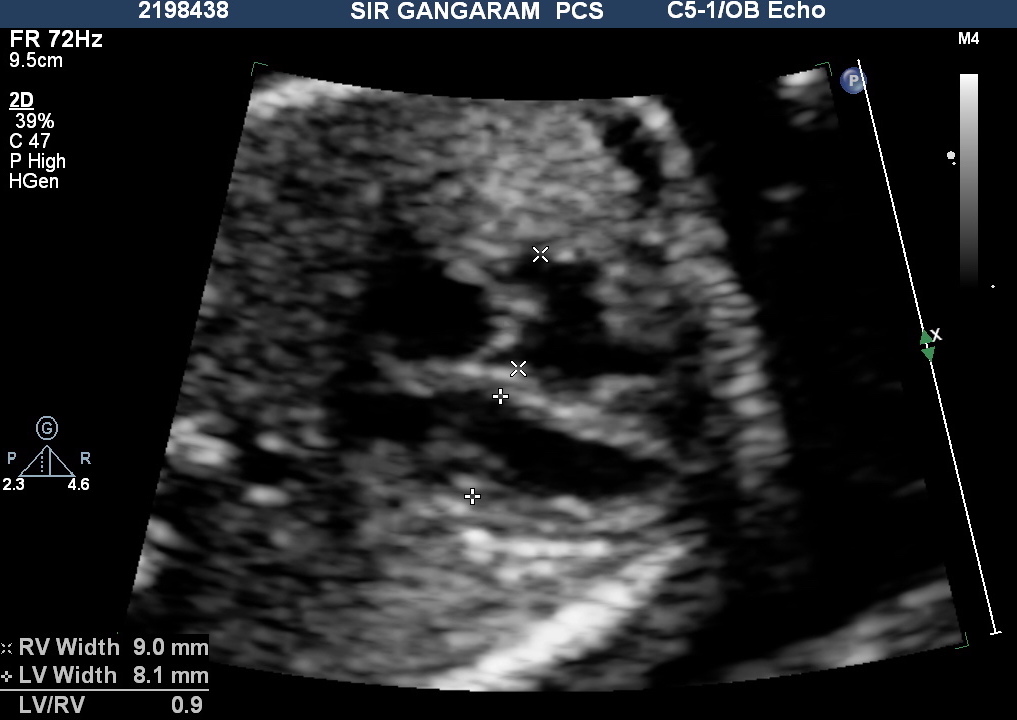

As the term suggests, Ventricle Disproportion means a noticeable discrepancy between the sizes of the ventricles. The routine cardiac screening mandates the display of a 4-chamber view and involves identifying the ventricles and atria. In a normal fetus, the ratio of Right Ventricle (RV) and Left Ventricle (LV) is near one throughout, in most cases.

As per classical teachings an RV to LV ratio of greater than 1.15 (LV to RV of <0.87 or 0.9) is considered abnormal and this holds value as a screening tool for RV enlargement. With these parameters, the positive predictive value is only 33% (Brown et al.). This is still valuable for screening of RV enlargement because it is easy to do, very reproducible and has less inter-observer variability.

- It is a good practice to measure LV and RV width in all fetuses during cardiac screening.

- If the ratio is more than 1.2 in the second trimester and more than 1.3 in the third trimester then Ventricle disproportion should be considered significant.